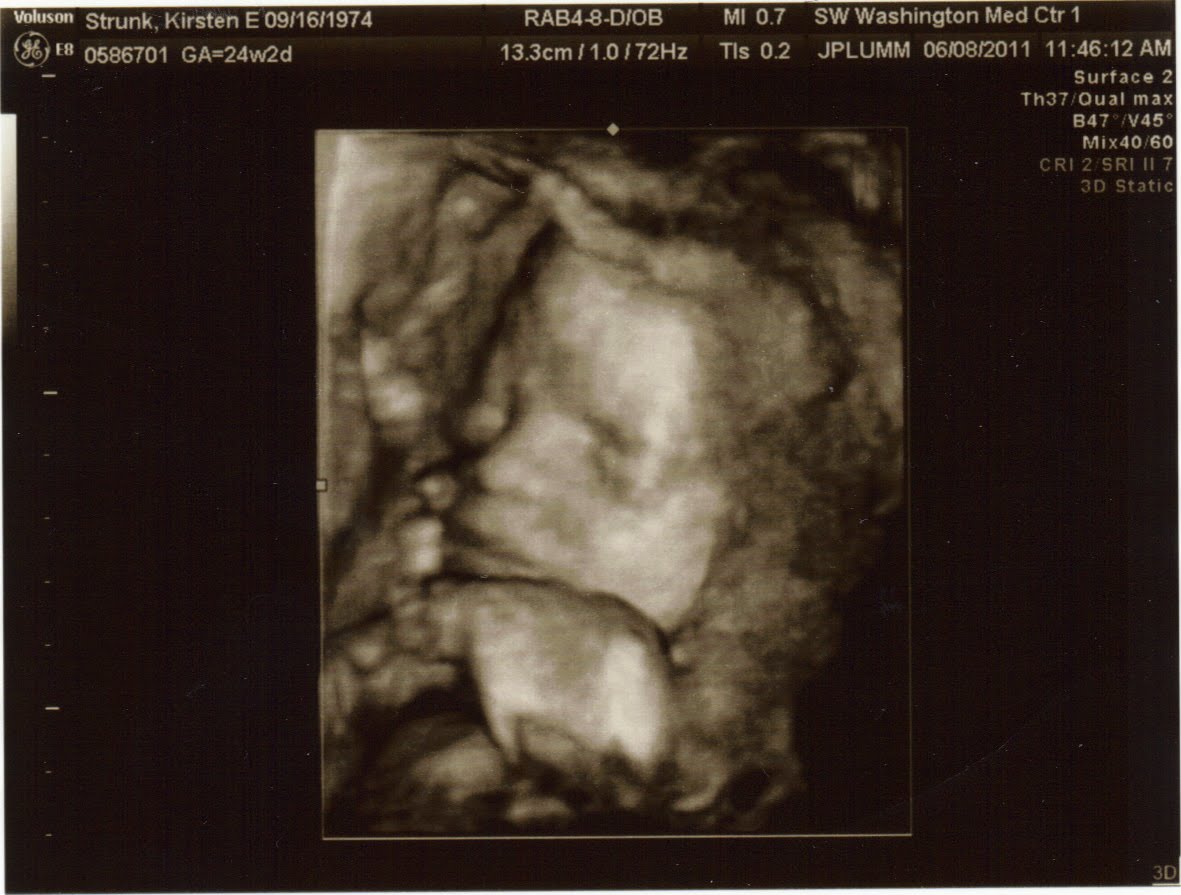

see....still a boy. And here is a cute little foot.

Had my (almost) 24 week apointment today. Gained about 4 pounds this month. 141.6 pounds. Blood pressure was good 117/70? My uterous is measuring 25 weeks. John's heartrate was 152. Because of the fact that his movement has slowed down......not stopped, the doctor wanted to do an ultrasound to make sure everything was ok. He was moving all around, his growth is good and his fluid level was good as well. All in all, baby John is doing well............and still a boy.